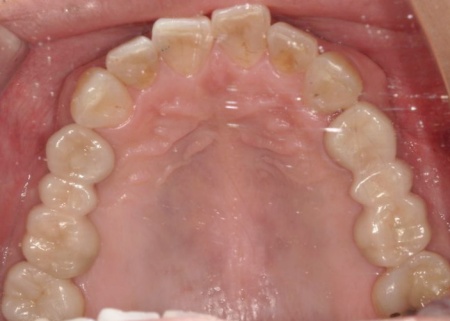

抜歯後は骨や歯茎の回復を待ち、口腔内の状態が安定した段階で、インプラント埋入手術へ進みました。

インプラントは、右上4番目と6番目の位置、左上4番目と6番目の位置に埋め込みます。

インプラントがしっかりと骨に定着したことを確認したら、精密な型取りを行い、ブリッジを作製して装着しました。

インプラント治療と併せて保存可能な歯の治療も進め、右上の一番奥の歯と右下の奥歯(前から5番目と6番目)に対して、細菌感染した神経を取り除いてから薬を詰める根管治療を行い、CAD/CAM冠という白い被せ物で修復しました。

さらに、上前歯(右上の犬歯から左上の犬歯まで)、右下の4番目の歯に対しては、虫歯治療を行っています。